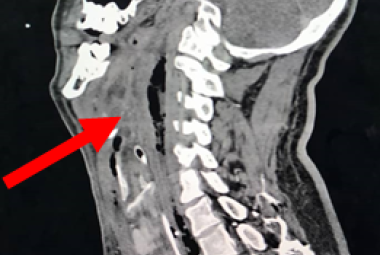

Iatrogenic tracheal injury (ITI) can occur in operations, intubation or tracheobronchial endoscopy. ITI associated with hemithyroidectomy is a very rare but devastating complication which can manifest immediately or in a delayed manner. The therapeutic approach can be conservative or surgical, but there is no universal consensus on the management. In this article, we described a rare case of intra-operative tracheal injury involving the cricothyroid membrane and right posterolateral first to second tracheal rings during right hemithyroidectomy, in which primary suturing was attempted. However, on the sixth day postoperatively, the patient developed neck swelling and respiratory distress owing to infection at surgical site complicated with temporary vocal cord palsy, which necessitated a tracheostomy. Patient was subsequently managed successfully with conservative management. We concluded that the therapeutic approach of ITI should be based on the time of presentation, clinical condition of the patient, size and location of the lesion.

FIGURE 1: Neck re-exploration revealing intact suture at the site of primary repair